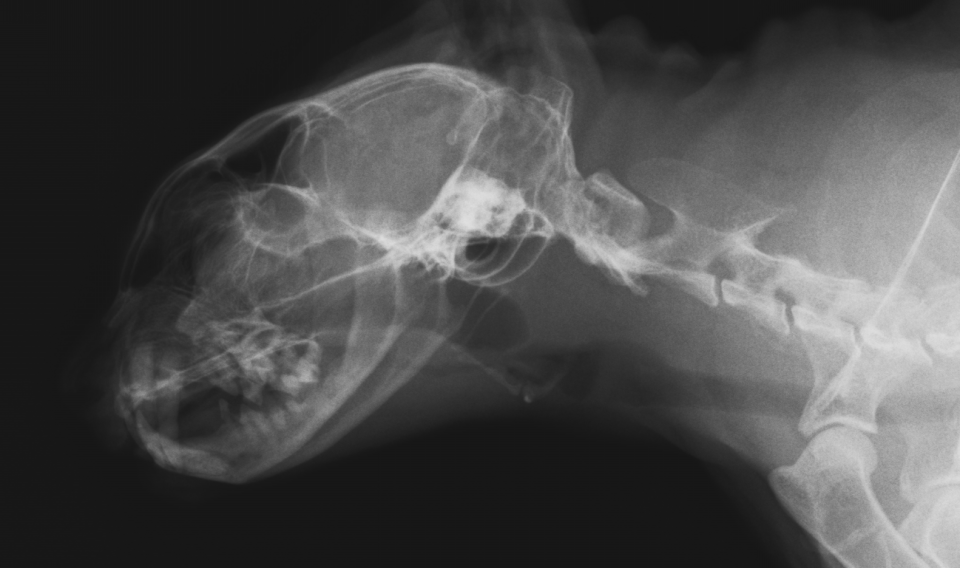

猫の鼻腔リンパ腫。

ねこちゃんで最も多い悪性腫瘍のリンパ腫がお鼻にできてしまったもの。クシャミなどの風邪症状や食欲不振、お顔の腫れで気づく場合が多いです。

他の臓器へのがん細胞の浸潤がない場合は放射線治療が最も効果的です。抗がん剤等を使用した化学療法も行われます。

case.1

初診時

左側鼻腔のX線不透過像を認める。

化学療法4週後。